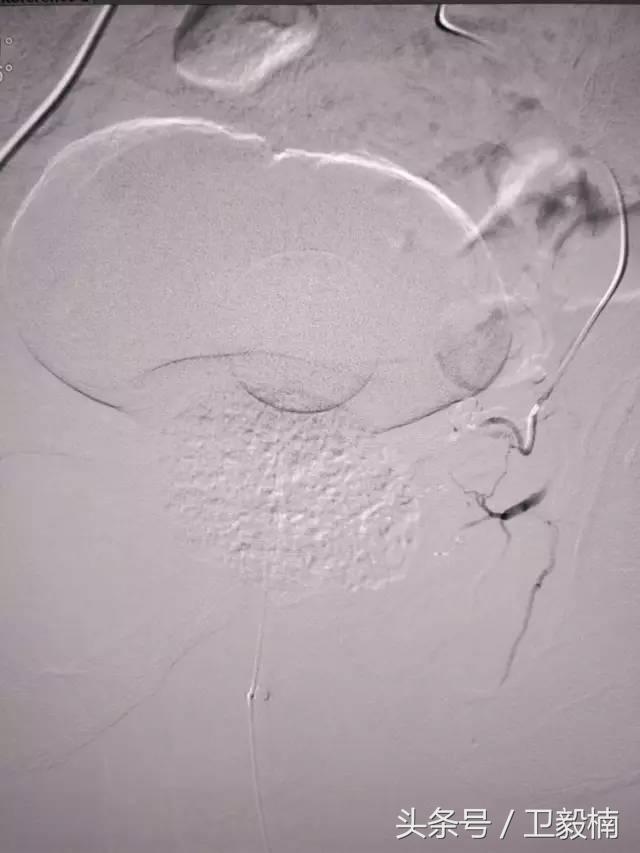

二、各类肿瘤的治疗:如肝癌、肺癌、食管癌、肾癌、胰腺癌、各种转移性肿瘤及妇科肿瘤、骨肿瘤等;

(2)肿瘤化疗 导管留置于供应肿瘤的动脉,滴注化疗药物,使局部用药浓度加大,避免或减轻化疗引起的全身反应。

2、经导管血管栓塞法(Transcatheter embolization)

经原血管造影的导管或特制的导管,将栓塞物送至靶血管内,一是治疗内出血如外伤性脏器出血、溃疡病、肿瘤或原因未明的脏器出血。另一是用栓塞法治疗肿瘤,因肿瘤循环部分或全部被栓塞物阻断,以达控制肿瘤之生长,或作为手术切除的一种治疗手段;亦可用于非手术脏器切除,例如注射栓塞物质于脾动脉分支内,即部分性脾栓塞,以治疗脾功亢进,同时不影响脾脏的免疫功能。

(1)选择性肿瘤供血动脉灌注化疗+栓塞治疗恶性肿瘤。